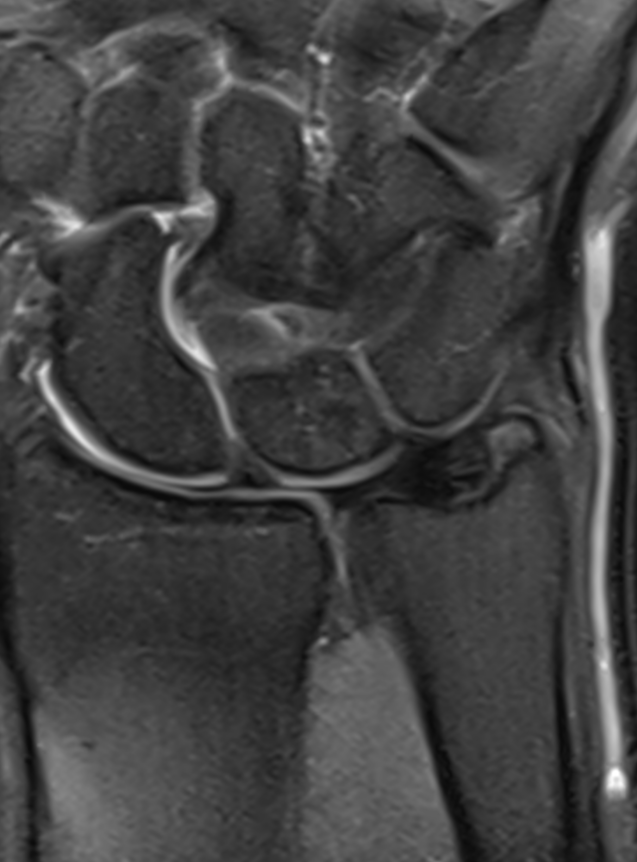

3. Normal Triangular Fibrocartilage Complex (TFCC)